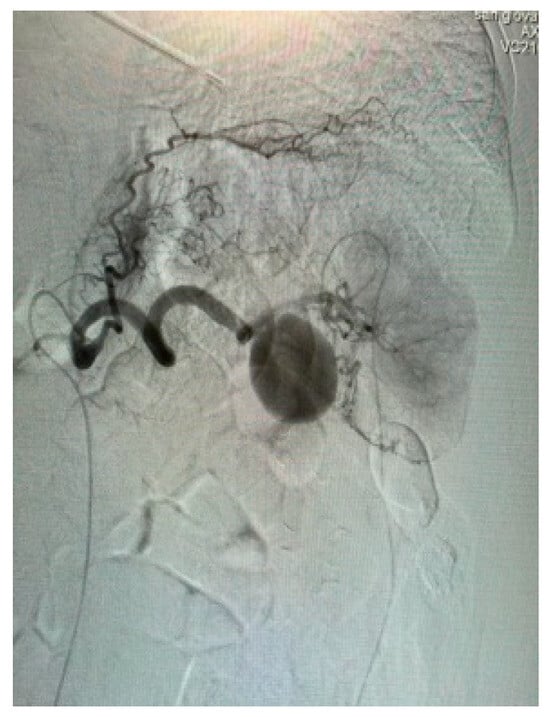

Appendix A.3. Clinical Case 3: Splenic Visceral Aneurysm